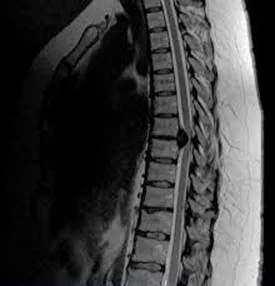

Боль в грудной клетке может быть вызвана грыжей диска. Но это крайне редкое явление.